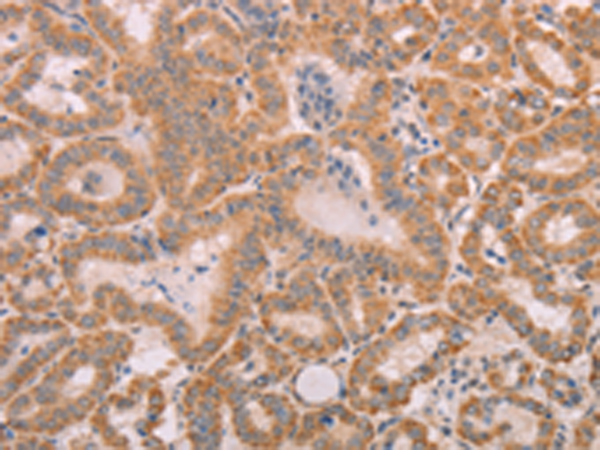

分类: 科研抗体货号: P00095别名: DWFC; JV5-1; MADH5应用: WB,IHC反应种属: Human, Mouse, Rat